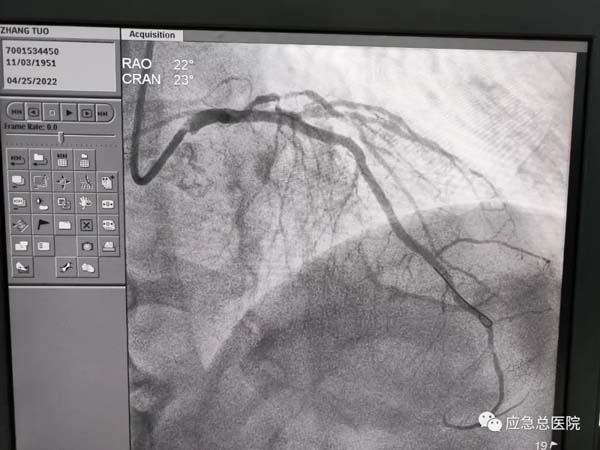

手术后

生命在接力。来到应急总医院后,为患者第一时间进行造影检查,结果提示:三支病变,前降支近端100%闭塞,也就是说供应心脏的三条血管均有严重的狭窄,而最主要的血管——前降支已经完全堵死,晚一点救治后果不堪设想。吴迪教授第一时间研判:务必马上开通闭塞血管,一刻都不能耽搁!因为应急总医院有一支经验丰富的介入团队,在吴迪教授的指导下,在范煜东副主任的熟练操作下,在张子龙副主任医师、张庆军主治医师及导管室护士、技师的通力配合下,病人的闭塞血管及时开通,如久旱甘霖般将鲜活的血液重新给濒临坏死的心肌细胞。手术一做完,病人就长舒一口气:“不疼了!舒服了!”在手术室门口焦急守候的家属,此刻喜极而泣。看看时间,从张大爷到光熙医院就诊,再转运到应急医院完成手术,仅用了50分钟。